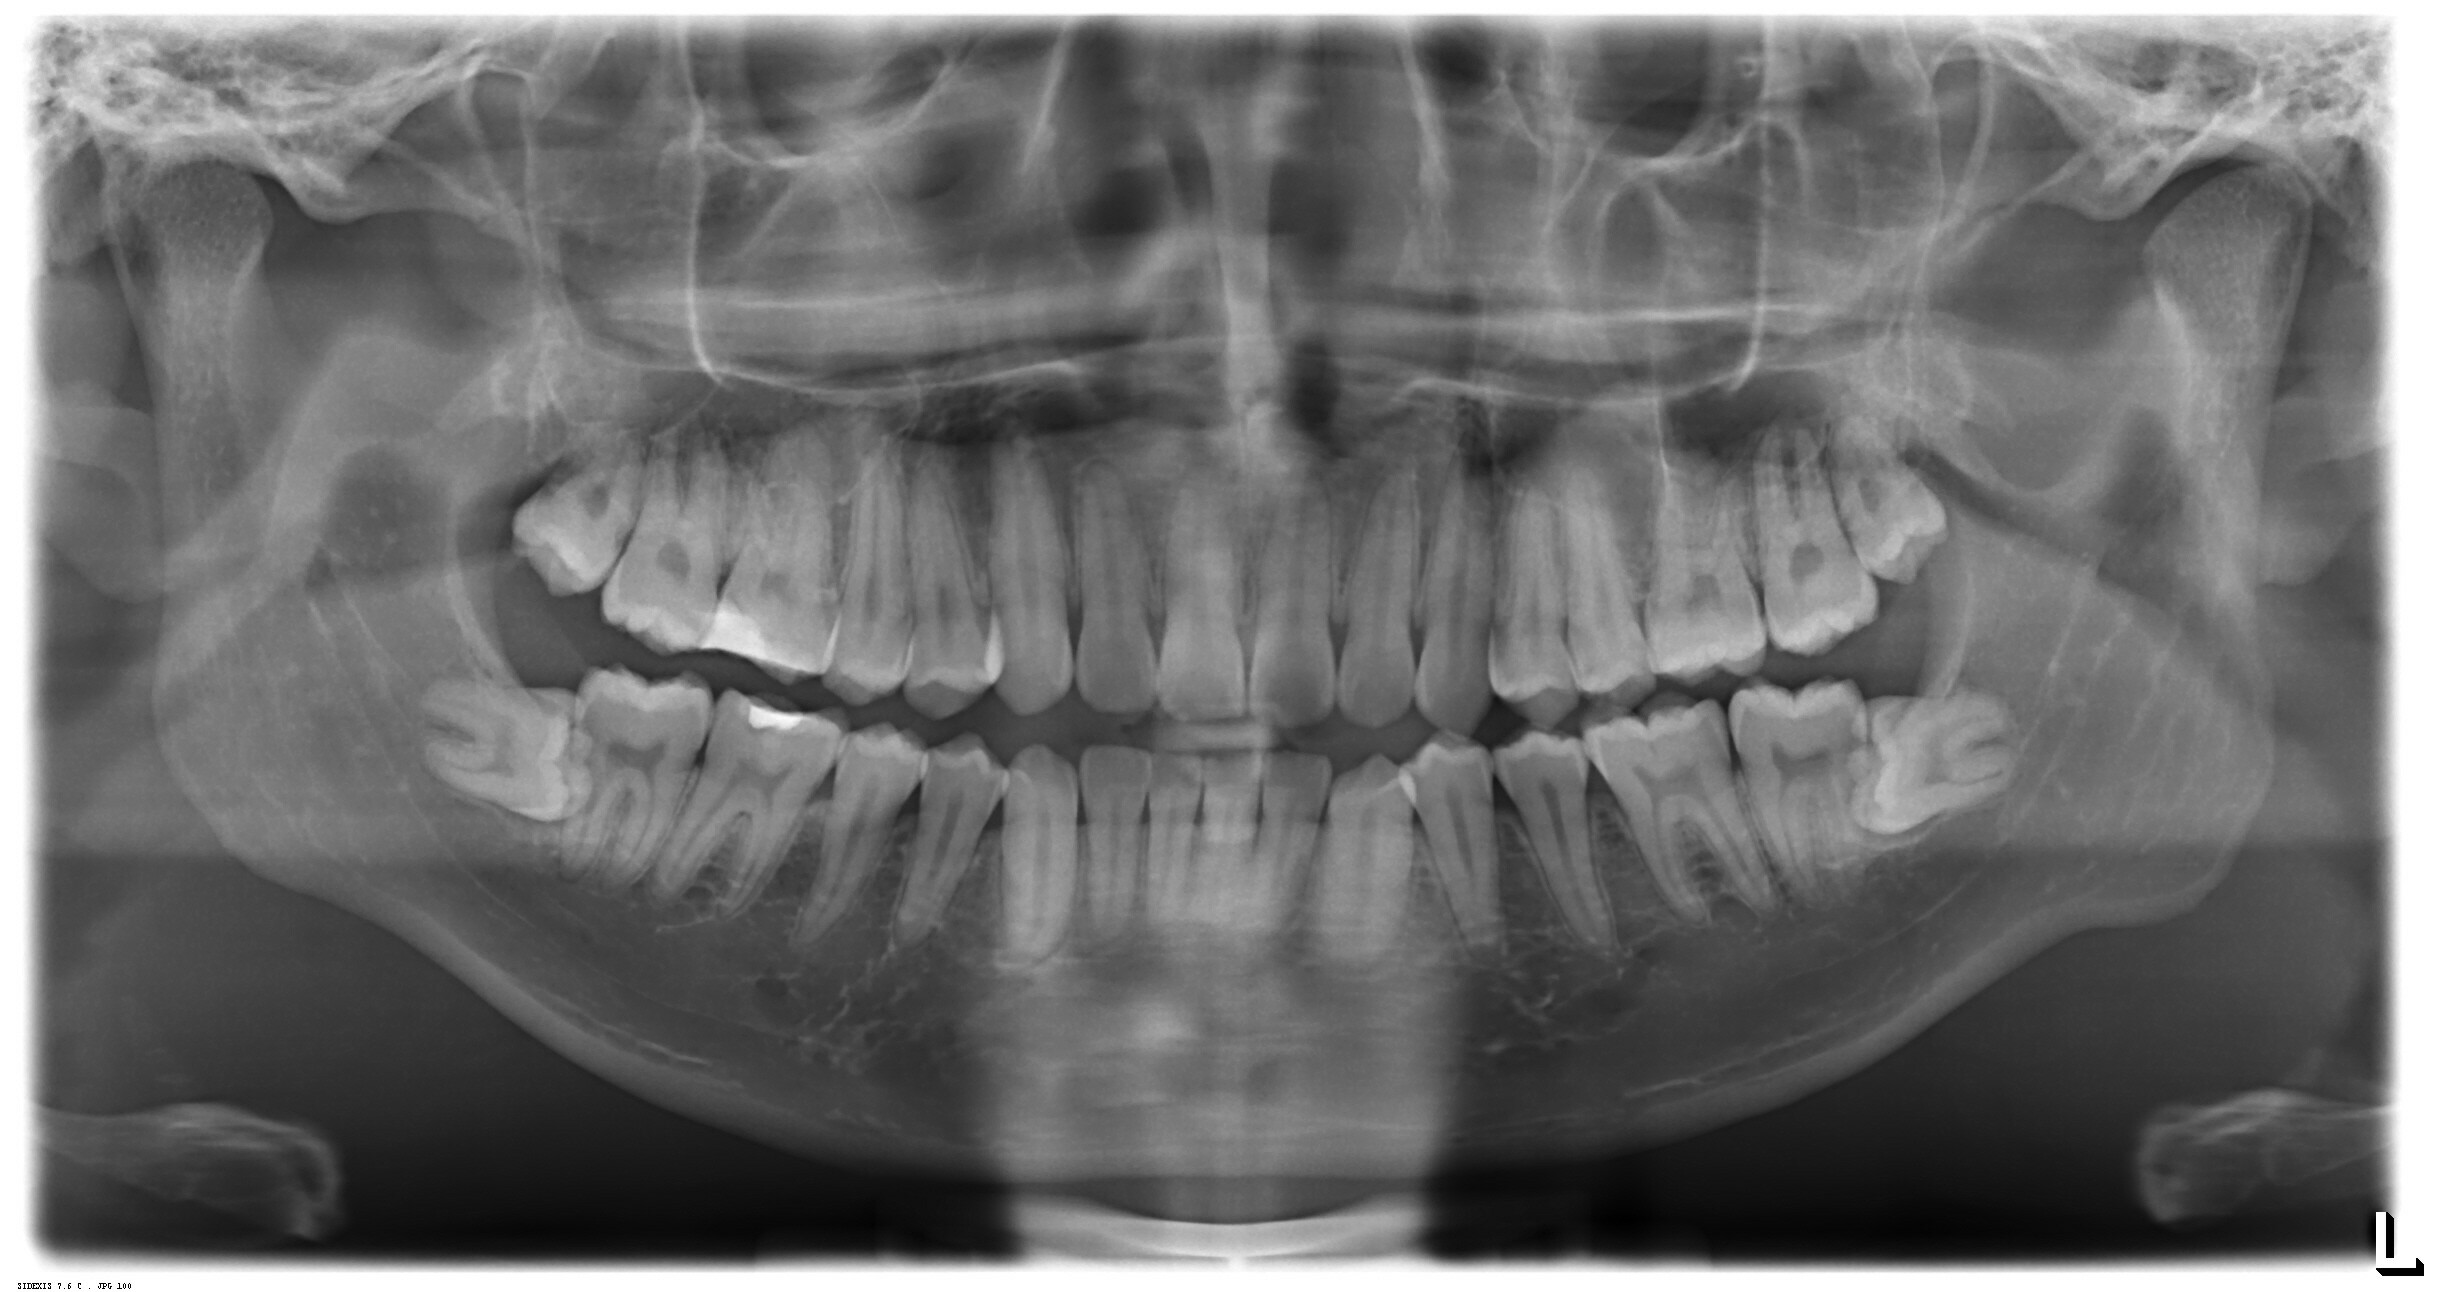

Submitted by kasuma9999 t3_10prqtx in mildlyinteresting

Reply to comment by kasuma9999 in Xray of my fully horizontal wisdom teeth. by kasuma9999